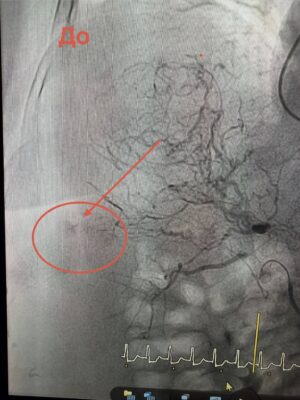

Через загрозливий стан проводити відкриту операцію було неможливо. Натомість лікарі застосували метод ендоваскулярної хірургії — за допомогою ангіографії визначили джерело кровотечі та виконали емболізацію судини, що дозволило її зупинити без масштабного хірургічного втручання.